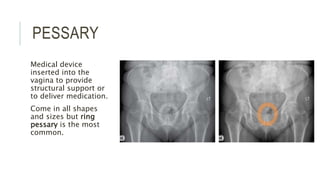

PESSARY

Medical device

inserted into the

vagina to provide

structural support or

to deliver medication.

Come in all shapes

and sizes but ring

pessary is the most

common.